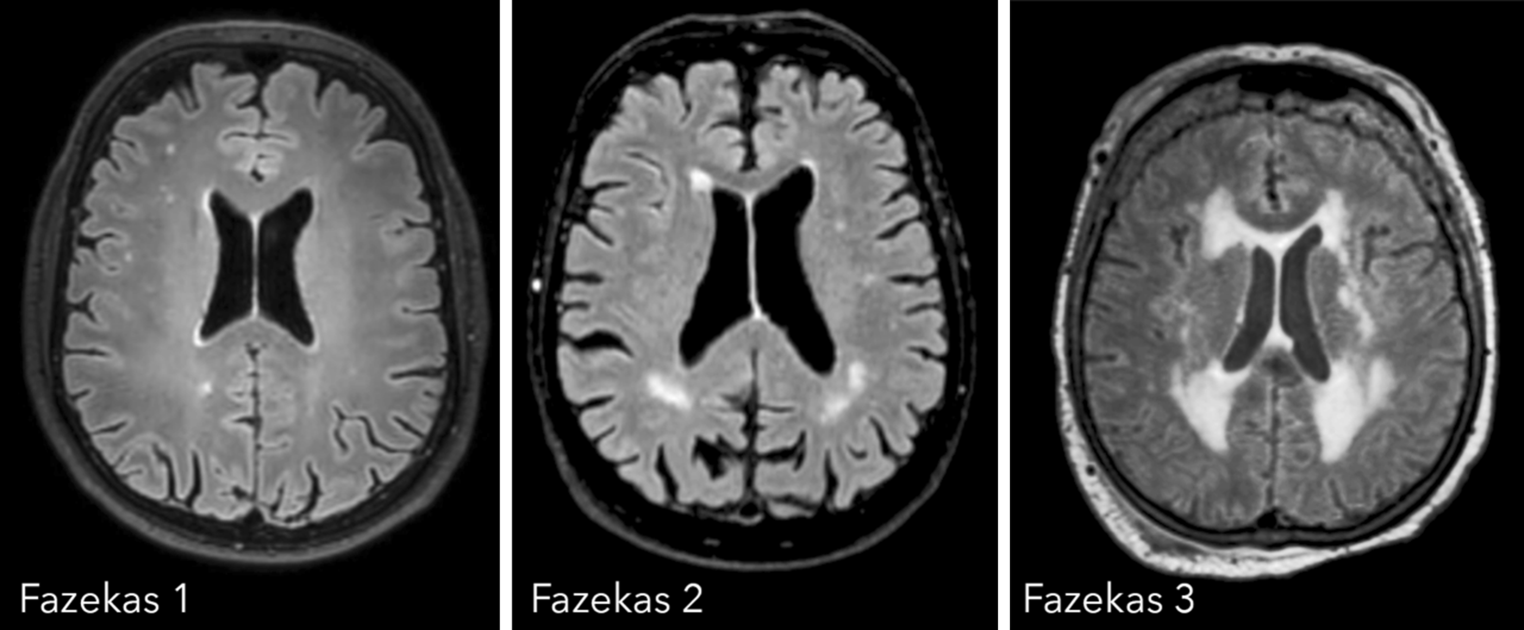

White matter changes

The most commonly used rating scale to determine the amount of white matter changes is the three-step Fazekas scale (illustrated in Fig. 4). It differentiates between small punctate (Fazekas 1), early confluent (Fazekas 2), and marked confluent (Fazekas 3) white matter lesions. For the diagnoses of vascular dementia, the more precise criteria of the National Institute of Neurological Disorders and Stroke and the Association Internationale pour la Recherché et l’Enseignement en Neurosciences (NINSDS-AIREN criteria) are taken into account [3].

Fig. 4

Fazekas scale

Bild vergrößern